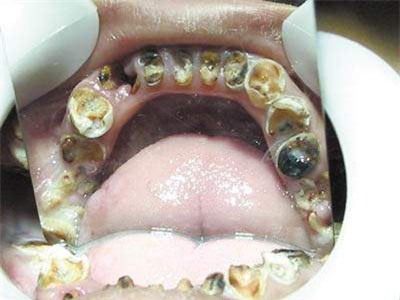

Bác sĩ đã không khỏi giật mình khi bé vừa mở miệng ra. Ông nói rằng cậu bé chẳng khác gì một ông già tí hon không còn răng, miệng lổn nhổn chân răng đen nhẻm và hơi thở có mùi.

Thông thường, trẻ em có khoảng 20 chiếc răng sữa. Sau khi kiểm tra sơ bộ, bác sĩ cho biết Quân Quân đã có 8 chiếc răng thối hoàn toàn chỉ còn chân răng bên trong.

Cùng lúc đó, 6 chiếc răng khác cũng bị biến dạng, vừa đen vừa vàng, sứt mẻ, không còn có thể nhận dạng được.